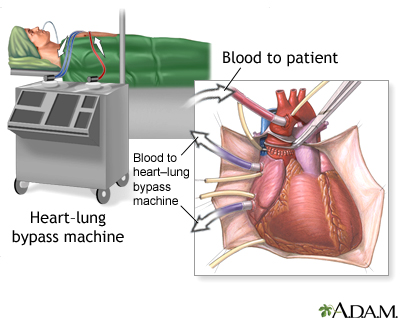

- Lung transplant, or in some cases, heart-lung transplant, if medicines do not work

For people with severe disease, lung transplant, or in some cases, heart-lung transplant can be considered.

Heart-lung transplant - series - Normal anatomy

Presentation